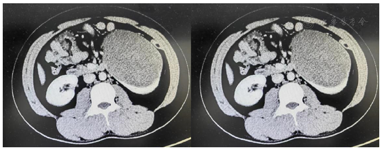

腹部增强CT(图1):左肾下极稍低密度肿物影大小约13.6 cm×8.5 cm×15.2 cm,边界清,内见多发片状低密度区,增强扫描强化不明显,内见条状明显强化血管影,病变将左肾实质撑开如杯口样改变、局部与左侧肾盂关系密切,向外突向肾周间隙生长,左肾见副肾动脉。CT诊断:左肾下极乏血供肿物,影像学表现不典型,定性困难;结合MRI图像,倾向良性或低度恶性间叶组织来源可能大。